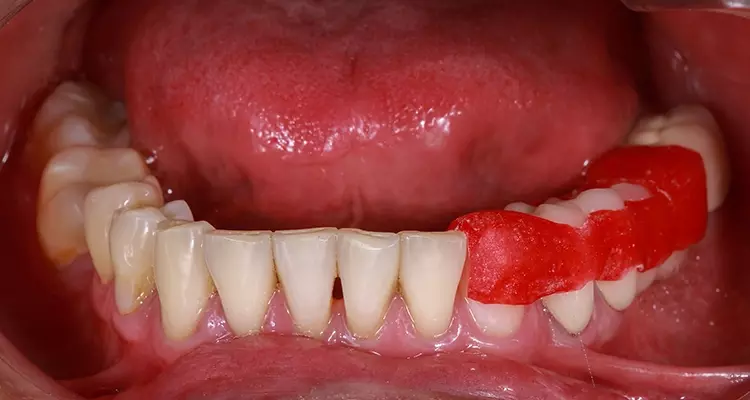

Die Form, das labiale Volumen und die Höhe für die Zahnkrone 11 wurden mit einer ästhetischen Apparatur aus selbsthärtendem Acrylharz (Pattern Resin, GC America) visualisiert. Ein Prototyp dient dem Zahntechniker als Platzorientierung bei der Modellierung des Wax-up und liefert auch Informationen über die korrekte Lagebeziehung der Oberkiefer- zu den Unterkieferfrontzähnen (Abb. 2).

Eine weitere Multifunktionsapparatur aus Pattern Resin (GC America) wurde hergestellt, um die zentrische Kondylenposition auf der Grundlage der ästhetischen, phonetischen und physiologischen Parameter mithilfe eines Deprogrammierers zu finden (Abb. 3). Die intermaxilläre Bissregistrierung mit Registriersilikon erfolgte bei eingesetzter Multifunktionsapparatur, um die geplante vertikale Dimension und funktionsorientierte Okklusionsebene festzulegen. Das Oberkiefermodell mit dem Kronenprototyp für Zahn 11 wurde mithilfe eines Gesichtsbogens (Elite, Bio-Art) in einen teiljustierbaren Artikulator (A7-Plus, Bio-Art) einartikuliert.